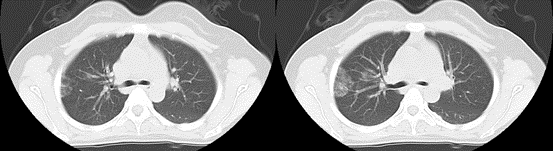

一位女性 26 岁的年轻女性来医院就诊,说“每到月经的时候自己就会无缘无故的咳嗽”,这期间并没有感冒的任何迹象。呼吸科医生就给她开了胸部CT检查。结果发现右肺上叶有片状的密度增高影。最后证实,原来是异位的子宫内膜在作祟。

1.影像学检查:如胸部CT扫描等,可发现肺部结节、肿块或胸腔积液等异常表现。